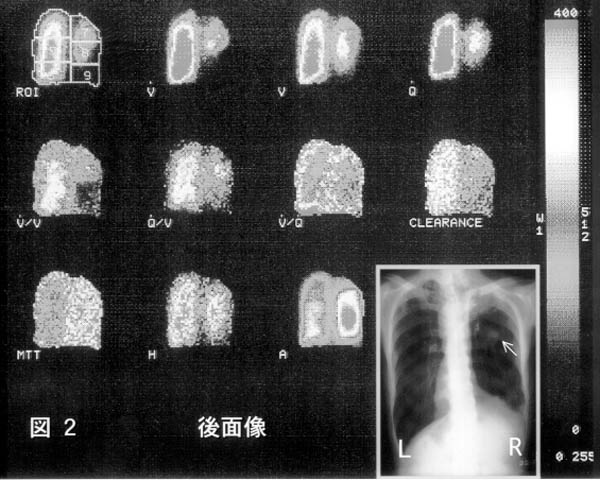

症例2.69歳、男性。

右下葉の肺門部近くに発生した肺癌(偏平上皮癌)症例である。99mTc-MAAと133Xeガスによる血流・換気シンチグラム(図2)では右肺門リンパ節と主気管支への癌浸澗による中・下肺野の血流および換気障害が示されている。胸部X線写真上の矢印は原発巣を示す。